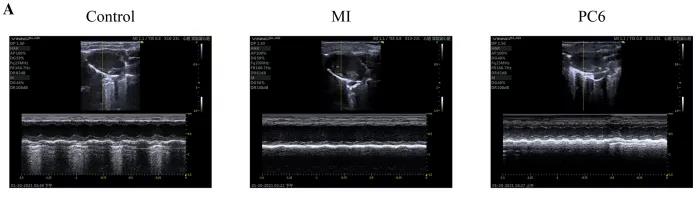

為了探討針刺PC6穴對心肌損傷的影響,作者首先評估了心功能和梗死面積。超聲心動(dòng)圖結(jié)果顯示MI組的EF(ejection fraction)和FS(fractional shortening)均較對照組明顯降低。PC6穴位治療后,EF和FS均增加。針刺治療5天后, 采用TTC染色檢測梗死面積。結(jié)果顯示,針刺治療顯著減小心肌損傷的大小。采用ELISA法測定反映急性心肌損傷的心肌特異性血清酶,包括心肌肌鈣蛋白T (cTnT)和心肌肌鈣蛋白I (cTnI)的水平。結(jié)果表明,心肌梗死術(shù)后cTnT和cTnI水平升高,針刺可顯著降低血清酶水平。